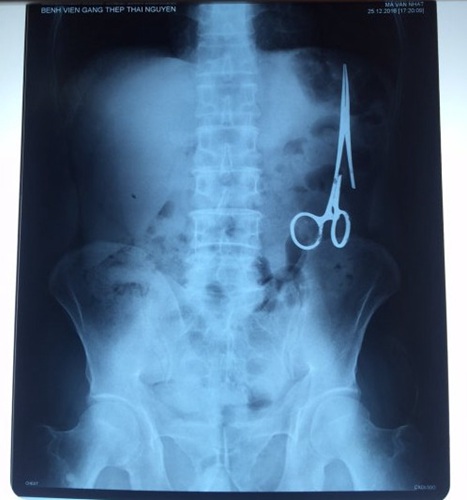

据越南青年报1月2日报道,在越南首都河内医疗专家的帮助下,越南东北部的太原省铸钢医院的医生日前从54岁患者M.V.N腹中取出一把医用剪刀。这把剪刀是此前曾为M.V.N手术的医生遗留的,已经在其腹中待了18年时间。

医务人员表示,这把剪刀遗留在病人腹部左侧,与结肠紧挨着。剪刀的把手已经生锈,部分器官也已经与剪刀粘连起来。但在过去多年中,M.V.N没有任何不适感觉,也从未因为留在腹中的剪刀引发的相关问题去看过医生。直到2016年12月,M.V.N因为遭遇了一场车祸,才到铸钢医院进行身体检查。

超声波检查显示,M.V.N的肠子中有个奇怪物体,看起来就像医用剪刀。M.V.N证实,他曾于1998年6月份在北江省综合医院接受手术,在此后也从未进行过任何手术。近来,他感到腹部有些疼痛,并试图通过服用药物治疗。12月27日,M.V.N回到北江省综合医院再次进行超声波检查,显示其腹部的确存在怪异物体。